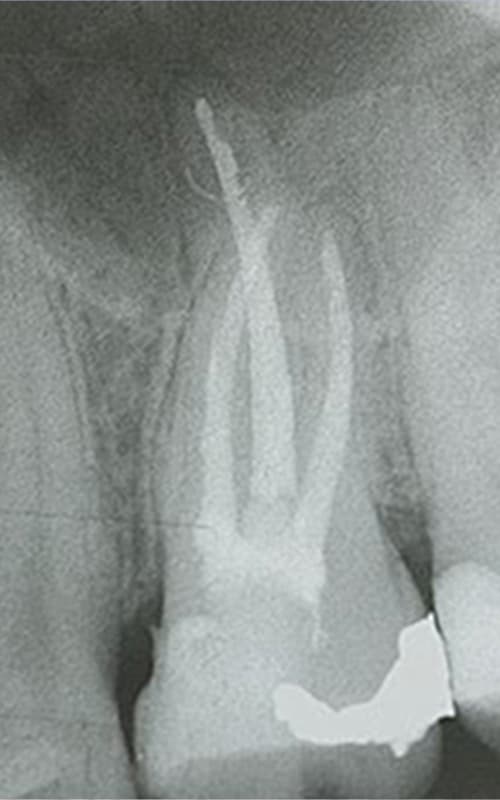

Sondierung der Kanalanatomie

Mit feinsten Stahlfeilen wird die Anatomie der Wurzelkanäle ertastet. Verkalkte Engstellen werden vorsichtig umgangen, um irreversible Verblockungen zu vermeiden.

Kanalerweiterung

Mit besonders elastischen und biegsamen Spezialbohrern werden die Kanäle schrittweise kontrolliert erweitert.

Röntgenkontrolle

Nach der erfolgreichen

Wurzelbehandlung wird zur Kontrolle ein Röntgenbild gemacht.